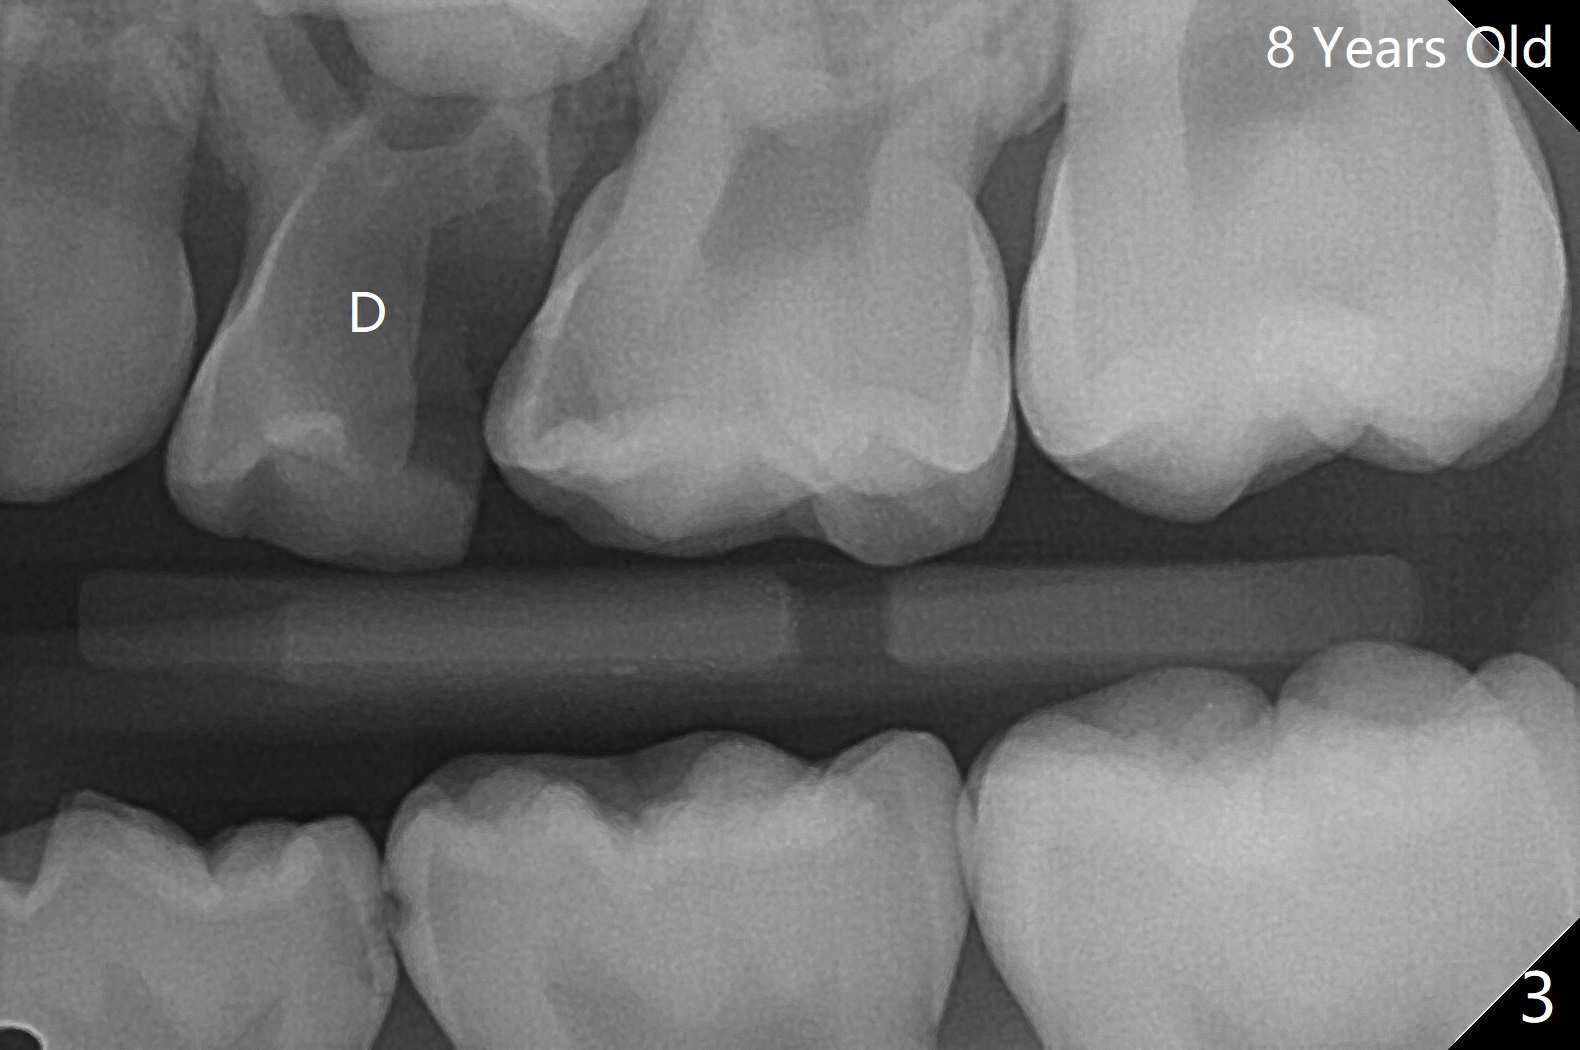

7岁女孩龋齿(图一)到八岁发展的严重(图二,三 (D))。为了有完整支抗,利用树脂(而不是不锈钢牙冠)保留左上第一乳磨牙(图六:D),以后可以安置矫正器。面部匀称(图七至十)。乳尖牙,第一恒磨牙:第一类咬合(图十一,十二)。左上前牙拥挤比右边轻,因为左上D龋齿破坏(图十三:D)。前牙扩弓时,右上D近中需要片切(^)。下颌拥挤轻(图十四),矫正器可以迟放置。